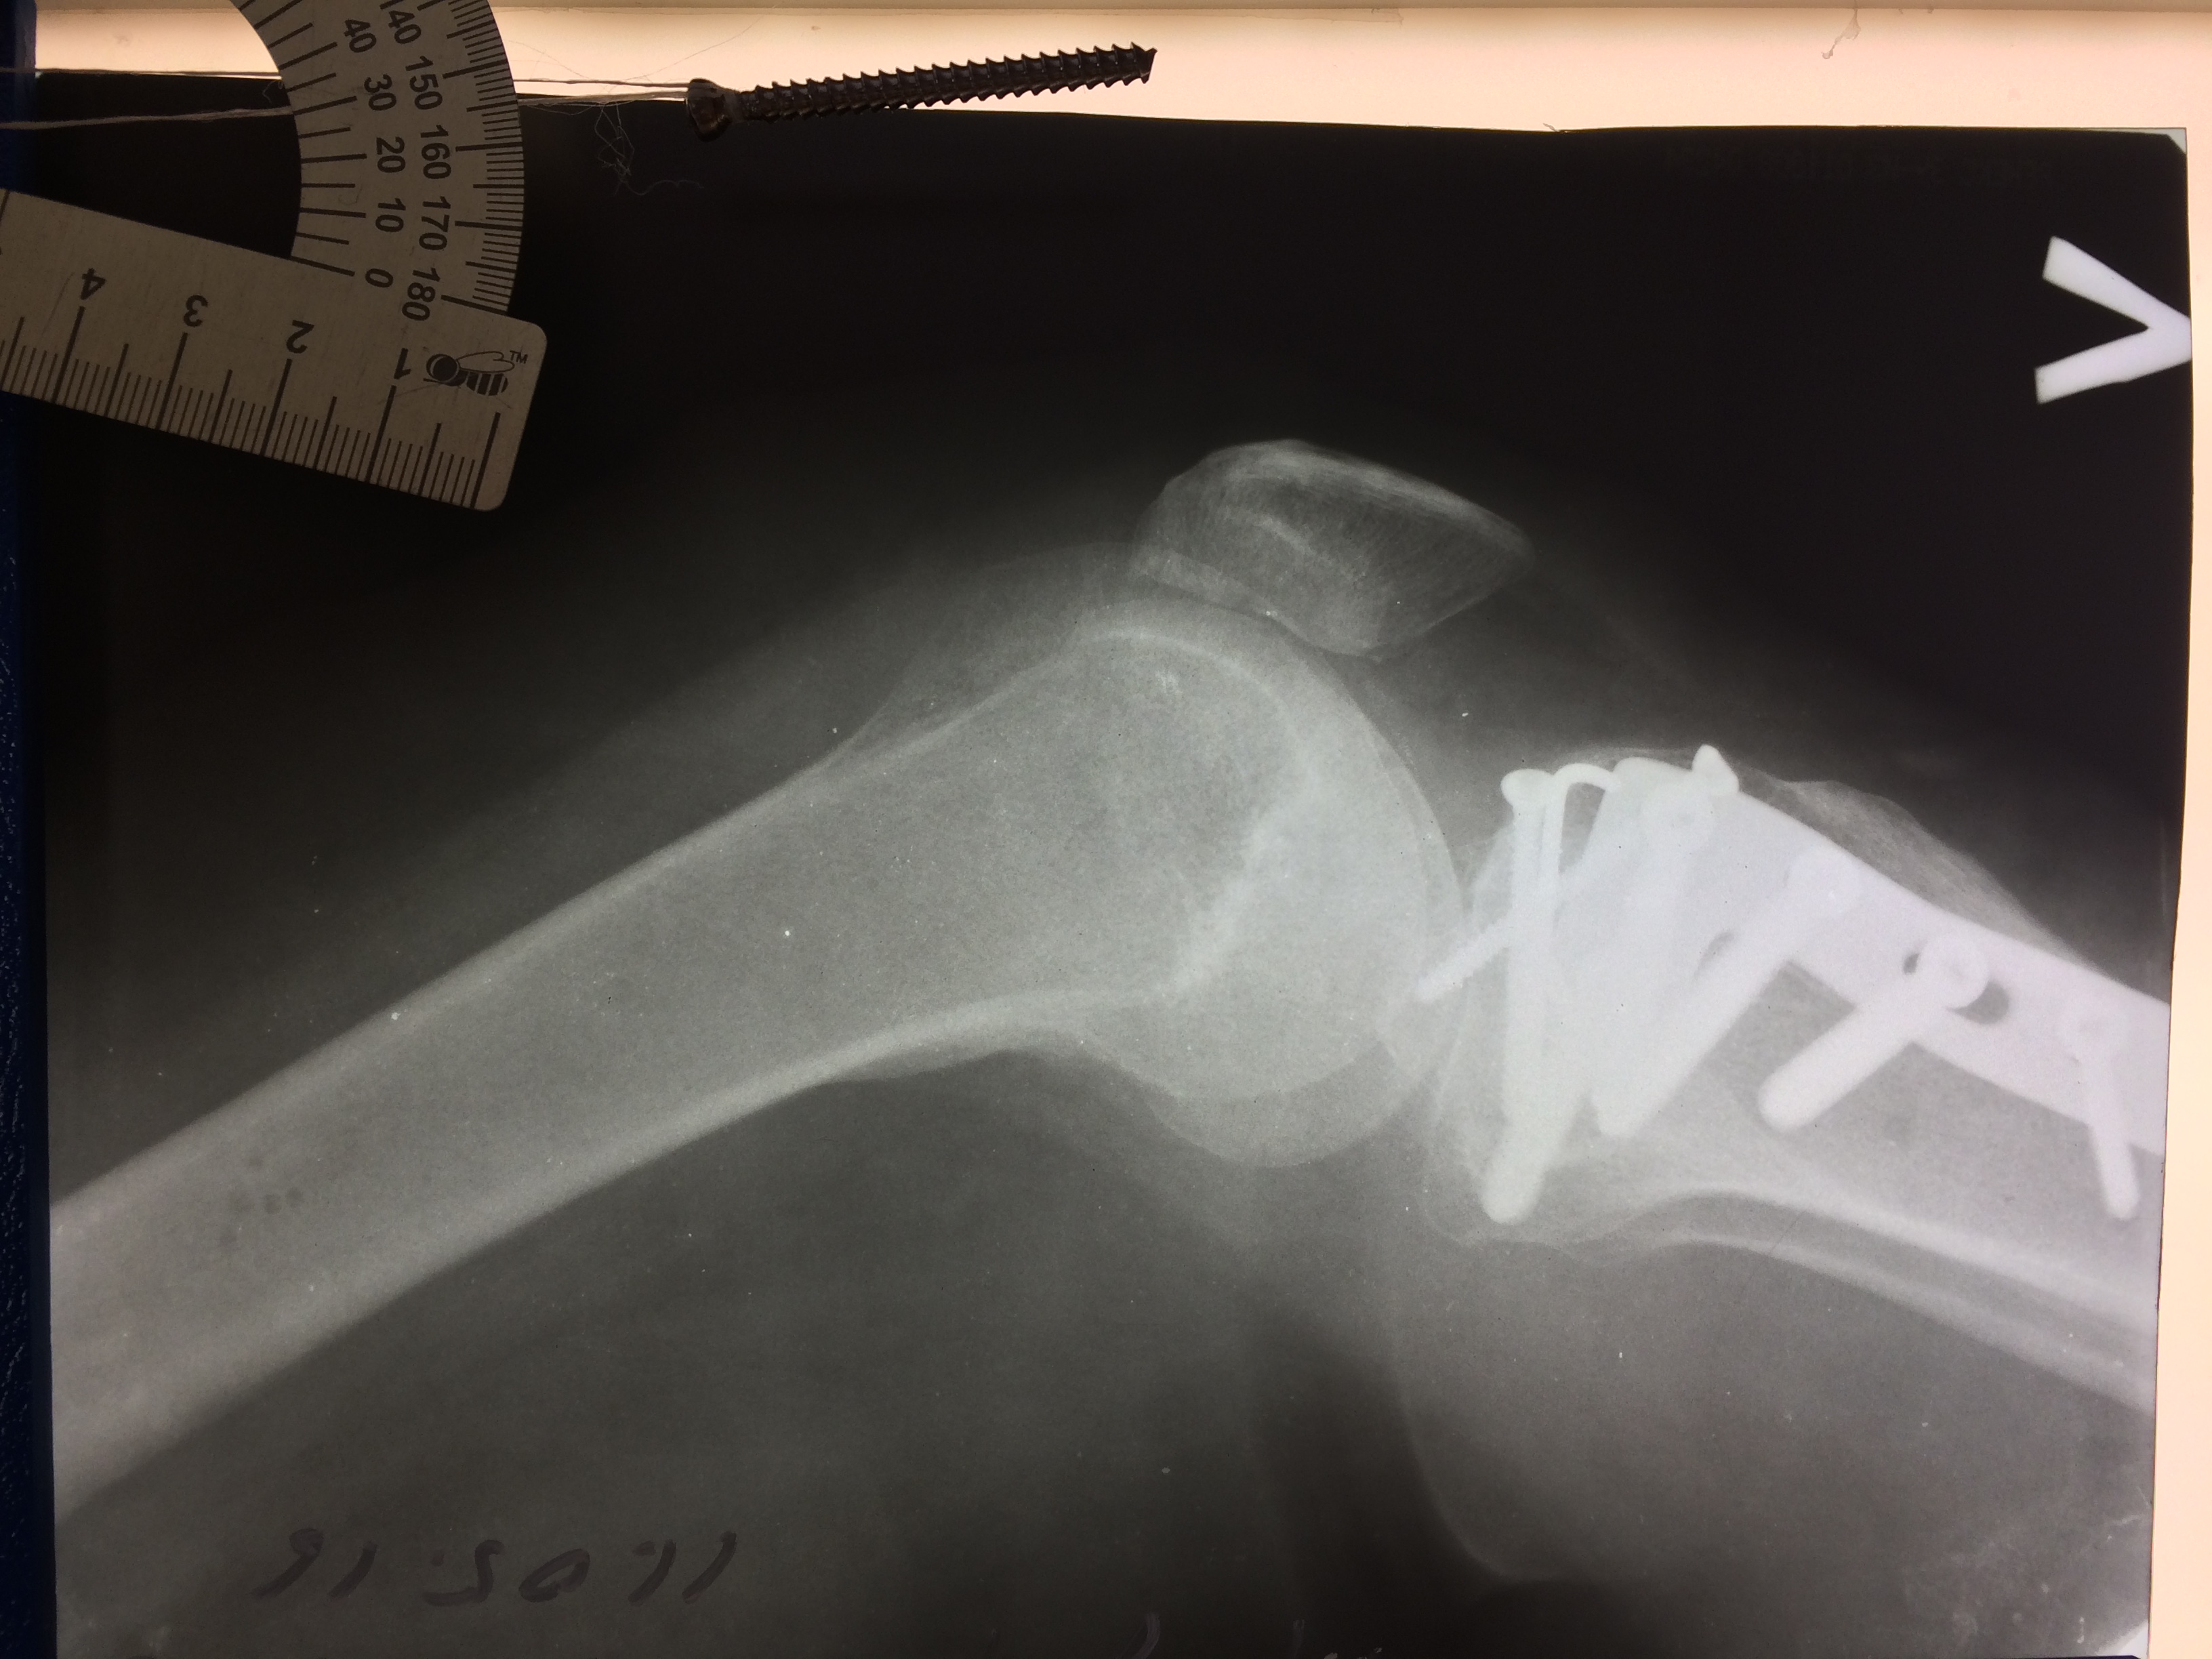

Операция - открытая репозиция, остеосинтез большеберцовой кости опорной пластиной с костной ксенопластикой маетриалом "Остеоматрикс". На контрольных снимках в три и шесть месяцев имеется консолидация перелома, миграции фиксатора нет, имеется остеоинтеграция ксенопластического материала. Функция коленного сустава полная.

Отдаленные результаты через 6 (шесть) месяцев